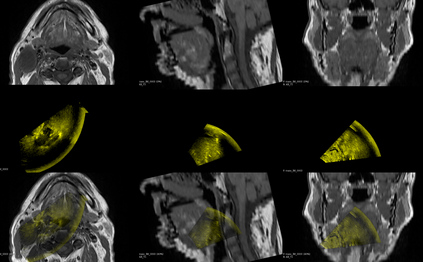

Purpose: Trans-oral robotic surgery (TORS) using the da Vinci surgical robot is a new minimally-invasive surgery method to treat oropharyngeal tumors, but it is a challenging operation. Augmented reality (AR) based on intra-operative ultrasound (US) has the potential to enhance the visualization of the anatomy and cancerous tumors to provide additional tools for decision-making in surgery. Methods: We propose and carry out preliminary evaluations of a US-guided AR system for TORS, with the transducer placed on the neck for a transcervical view. Firstly, we perform a novel MRI-transcervical 3D US registration study. Secondly, we develop a US-robot calibration method with an optical tracker and an AR system to display the anatomy mesh model in the real-time endoscope images inside the surgeon console. Results: Our AR system reaches a mean projection error of 26.81 and 27.85 pixels for the projection from the US to stereo cameras in a water bath experiment. The average target registration error for MRI to 3D US is 8.90 mm for the 3D US transducer and 5.85 mm for freehand 3D US, and the average distance between the vessel centerlines is 2.32 mm. Conclusion: We demonstrate the first proof-of-concept transcervical US-guided AR system for TORS and the feasibility of trans-cervical 3D US-MRI registration. Our results show that trans-cervical 3D US is a promising technique for TORS image guidance.